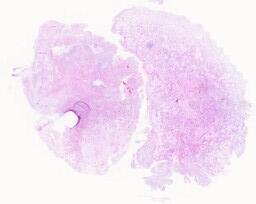

大体所见: 灰白灰红不整组织1块,大小3.4cmx2.6cmx1.6cm,表面光,包膜完整,切面灰白灰红实性质中。

免疫组化: Vimentin+,CD34+,Syn-,CD56-,Desmin-,NSE-,SMA+,Ki67约5%。